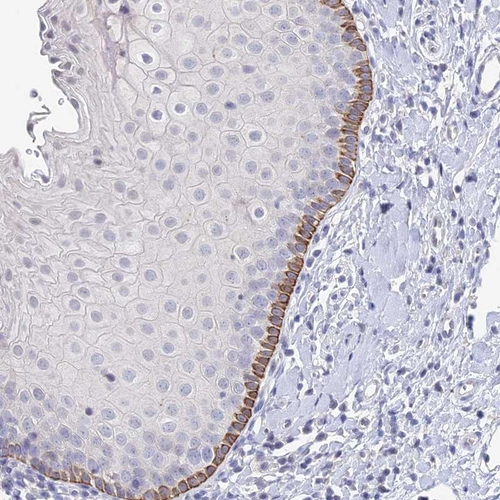

Immunohistochemical staining of human esophagus shows strong cytoplasmic positivity in squamous epithelial cells.